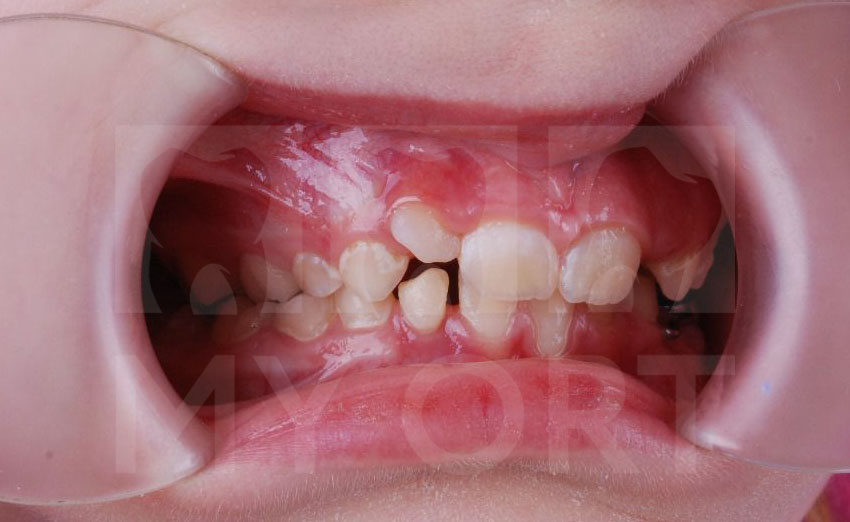

Родители семилетней девочки обратились ко мне, врачу-стоматологу, ортодонту, гнатологу, с жалобами на неправильный прикус. У ребенка начали прорезываться постоянные зубы и родителей беспокоило отсутствие места для нормального роста зубов.

Компьютерная томография (КТ) показала у ребенка — дистальный прикус, ретрузию и кант окклюзионной плоскости зубов.

Чего мы смогли добиться во время лечения

1. Улучшение лицевого профиля.

2. Устранён дефицит места для зубов.

3. Скорректирован наклон окклюзионной плоскости.

4. Уменьшена ретрузия (нормализация высоты прикуса).

5. Исправлен дистальный прикус.

6. Частично устранена скученность зубов.

Улыбка До и После

Посмотрите, что у нас получилось:

До и после